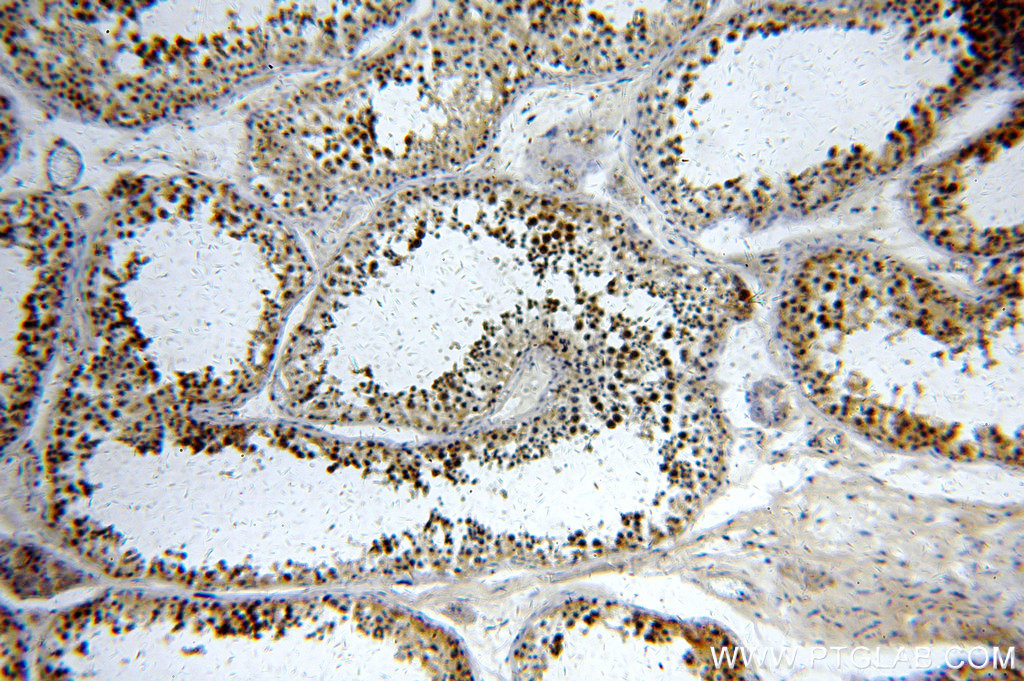

| Positive IHC detected in | human testis tissue Note: suggested antigen retrieval with TE buffer pH 9.0; (*) Alternatively, antigen retrieval may be performed with citrate buffer pH 6.0 |

| Immunohistochemistry (IHC) | IHC : 1:20-1:200 |